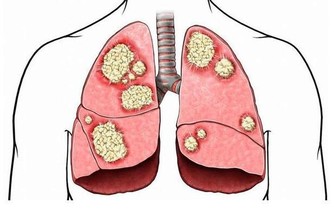

如果患者進入了腎病五期,腎功能已經大幅衰竭時,只採取藥物治療和飲食控制遠遠不夠。因為這時的腎臟基本失去了過濾和排除毒素的功能,需要通過腎透析或腎臟移植才能維持正常運轉,但是這兩種方法很有可能會引起嚴重的並發症。